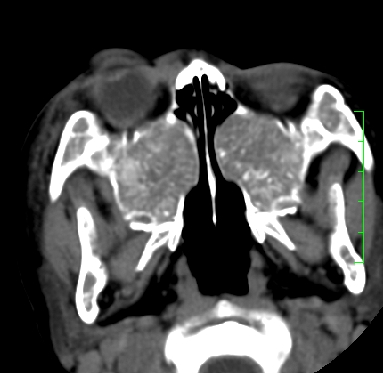

标题: PED1889:上颌窦病变

m,10y,外伤做ct

骨纤?

支持;骨纤,有皮肤色素沉着,性早熟时为albright综合征。

霉菌性鼻窦炎

骨化性纤维瘤可能性大。(与骨纤的鉴别:常见于面颅骨,多骨发病)